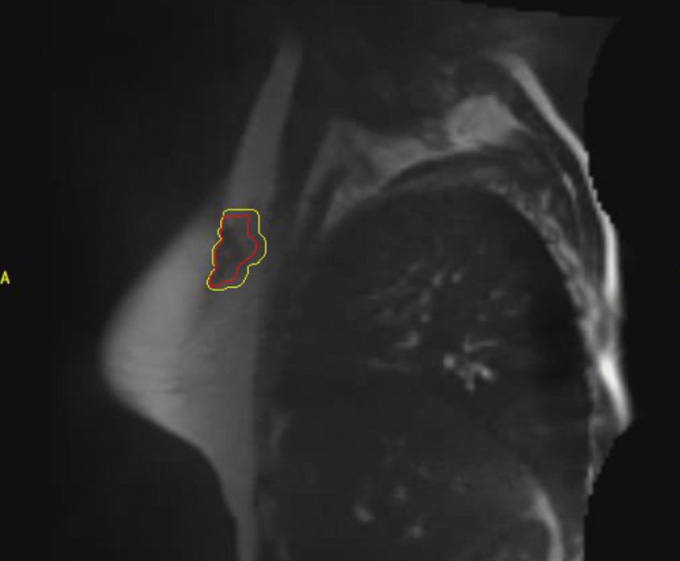

A representative surgical cavity target volume seen from an MRI image acquired on-table on the day of the radiation treatment. The MRI scans in both the axial and sagittal planes are shown. The surgical cavity is outlined in red. (Credit: John Ng, Ryan Pennell and Silvia Formenti. Front. Oncol., 23 November 2022)

MRI offers significant advantages over the CT scans traditionally used for prone partial breast irradiation. “A CT scan sometimes is not very good at seeing where the tissue changes, meaning that if you look at the breast after surgery with a CT scan, you may not be able to precisely determine where the surgery occurred,” Dr. Ng explains. MRI is better at delineating soft tissue contrast and taking a more detailed picture of the surgical cavity. Also, doing a CT scan entails delivering very low but, nonetheless, safe doses of radiation to the entire body — an MRI scan does not.

The recently published study demonstrated the feasibility of using MRI technology for prone partial breast irradiation and achieved excellent results. The treatments were successfully delivered and the patients only experienced temporary, minimal side effects. Dr. Ng, Dr. Formenti, and Ryan Pennell, PhD, Chief Medical Physicist in Radiation Oncology at NewYork-Presbyterian/